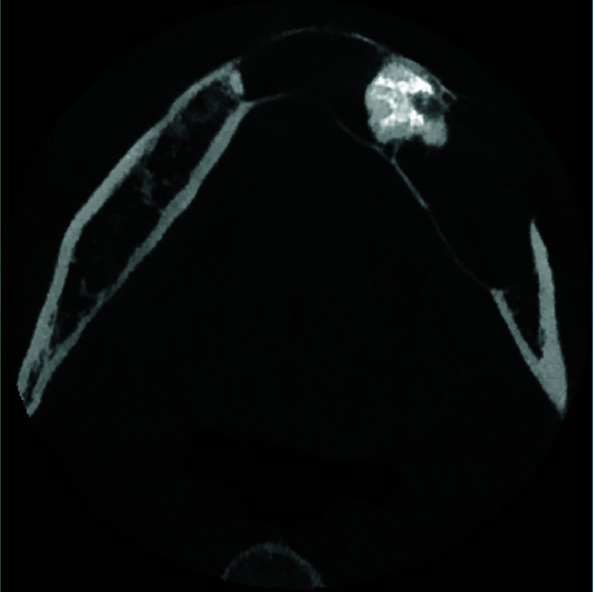

Hybrid lesions of jaws are rare entities defined as two different lesions co-occurring in the same location, with identical histopathological origin. Ameloblastoma, calcifying cystic odontogenic tumor and odontoma are among the most common lesions that have been reported to combine with other lesions. In this study, a hybrid lesion of odontogenic keratocyst (OKC) and odontoma in the mandible of a forty-five years old male reported. Additional to the rarity of this hybrid lesion, the present case had unique radiologic features, including atypical location and extension of the lesion and profound knife-edge root resorption of the teeth in the area, which was not a common feature for any of the two lesions. The surgical procedure was marsupialization to reduce the size of the lesion. As a result of the surgery, the healing of the surgical wound was uneventful. In addition, careful follow-up for the patient was conducted, which had no recurrence till now (after 15 months).